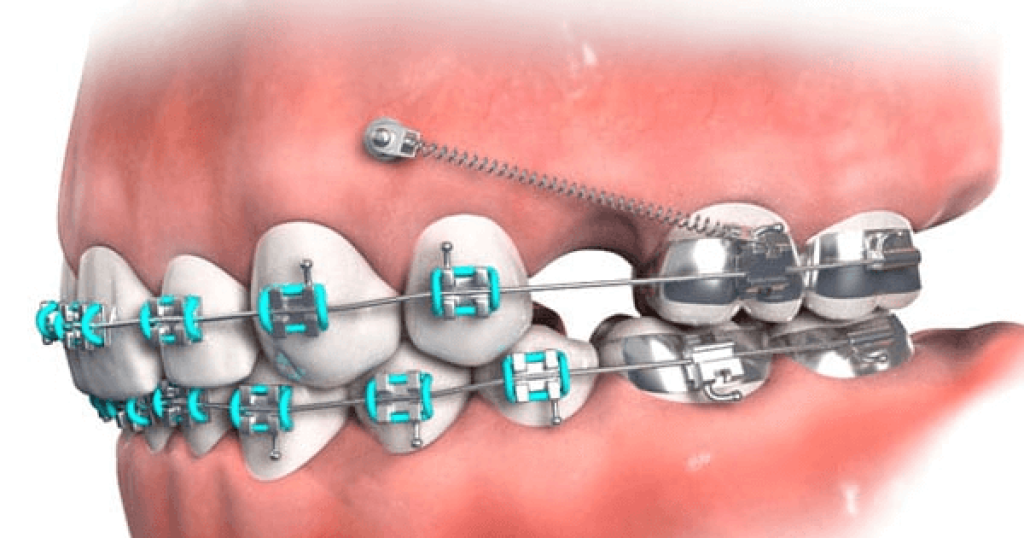

Trong chỉnh nha, đóng khoảng là quá trình bác sĩ sử dụng lực kéo từ dây cung, lò xo hoặc thun chỉnh nha để di chuyển các răng lại gần nhau, lấp đầy khoảng trống trên cung hàm. Những khoảng trống này thường được tạo ra có chủ đích trong kế hoạch điều trị, giúp răng có không gian dịch chuyển chính xác hơn. Nhờ đó, các răng sẽ dần sắp xếp đúng vị trí trên cung hàm. Đây là bước quan trọng để hoàn thiện cấu trúc răng và chuẩn bị cho giai đoạn tinh chỉnh khớp cắn.

Giai đoạn đóng khoảng được xem là một bước then chốt trong kế hoạch chỉnh nha. Đây là thời điểm các khoảng trống trên cung hàm dần được lấp đầy nhờ lực kéo từ hệ thống mắc cài, dây cung hoặc thun chỉnh nha. Khi các răng di chuyển đúng hướng và đúng vị trí, cấu trúc cung hàm sẽ trở nên cân đối và ổn định hơn. Điều này tạo nền tảng quan trọng để quá trình niềng răng đạt được kết quả tối ưu.

Nếu giai đoạn đóng khoảng được thực hiện đúng kỹ thuật, răng sẽ dịch chuyển từ từ, ổn định và hạn chế tối đa các biến chứng không mong muốn. Nhờ đó, các bước tiếp theo như tinh chỉnh khớp cắn và điều chỉnh chi tiết vị trí răng sẽ diễn ra thuận lợi hơn. Ngược lại, nếu lực kéo không được kiểm soát tốt, răng có thể di chuyển sai hướng hoặc mất nhiều thời gian để điều chỉnh lại. Điều này có thể khiến tổng thời gian niềng răng kéo dài hơn so với kế hoạch ban đầu.